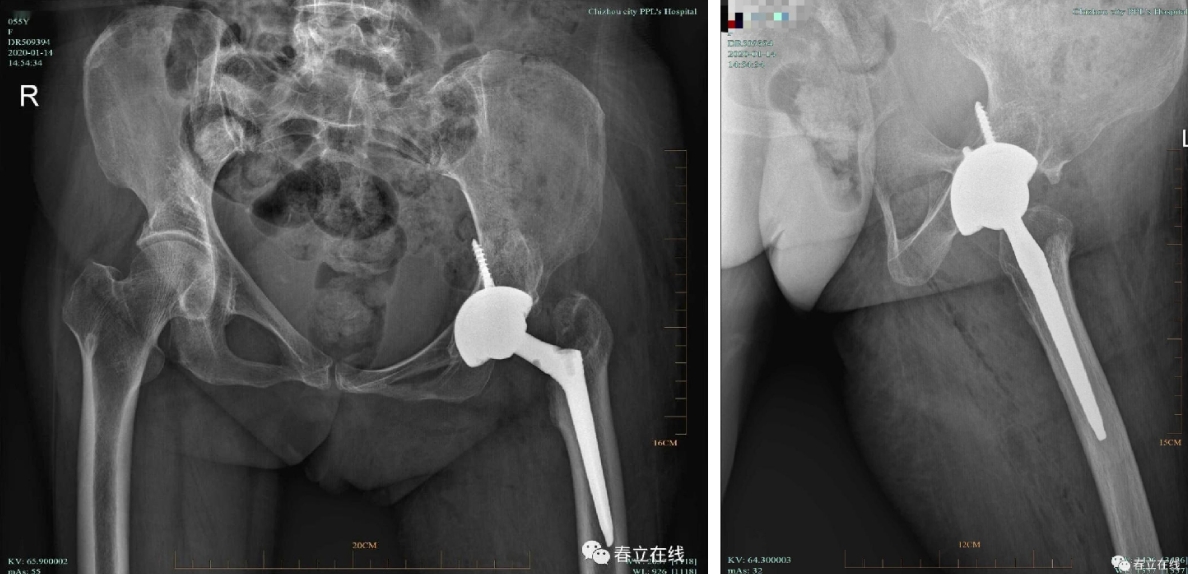

Total hip/knee arthroplasty is the most effective treatment for severe joint diseases. As a mature therapy widely used globally, it is hailed as a key milestone in 20th-century orthopedic development.